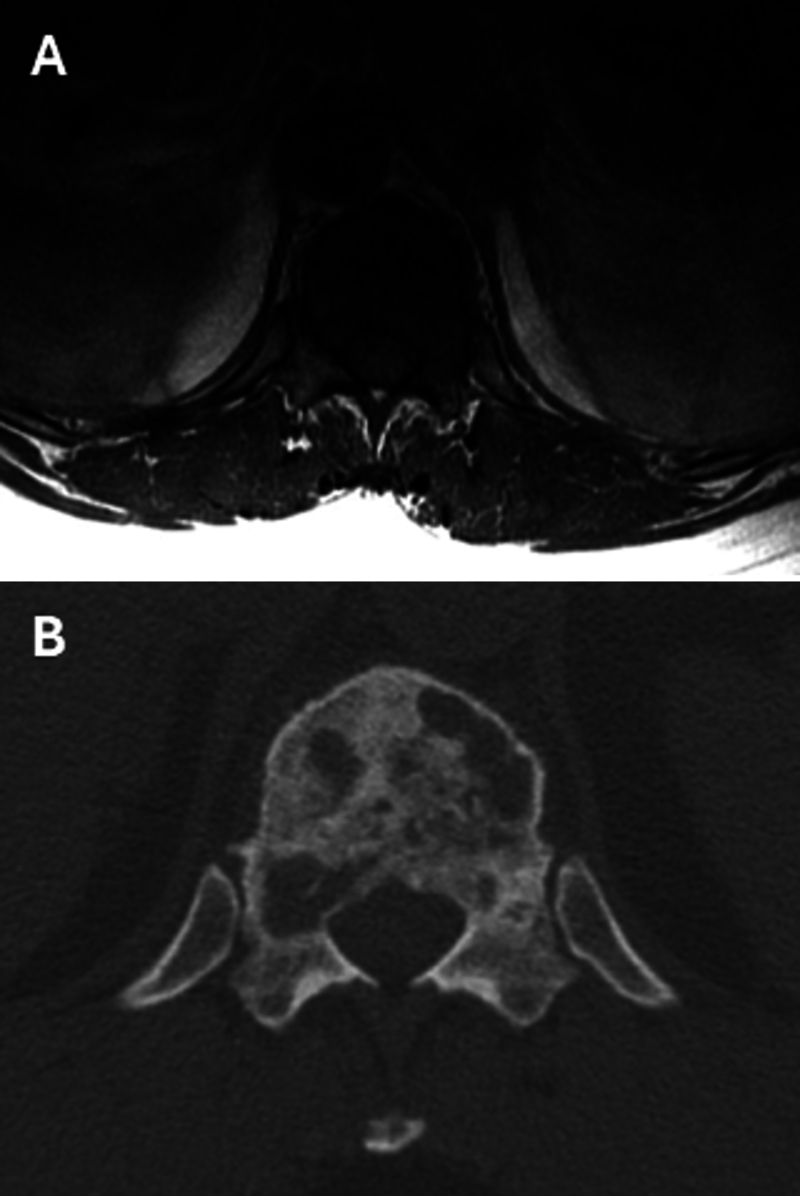

Observations: This report details a unique case of thoracic PMHE in a 60-year-old woman managed with a multistaged surgical approach, including preoperative embolization and en bloc spondylectomy. The authors describe the patient's clinical presentation, radiographic findings, surgical technique, and postoperative course, highlighting the role of en bloc resection in achieving tumor control.